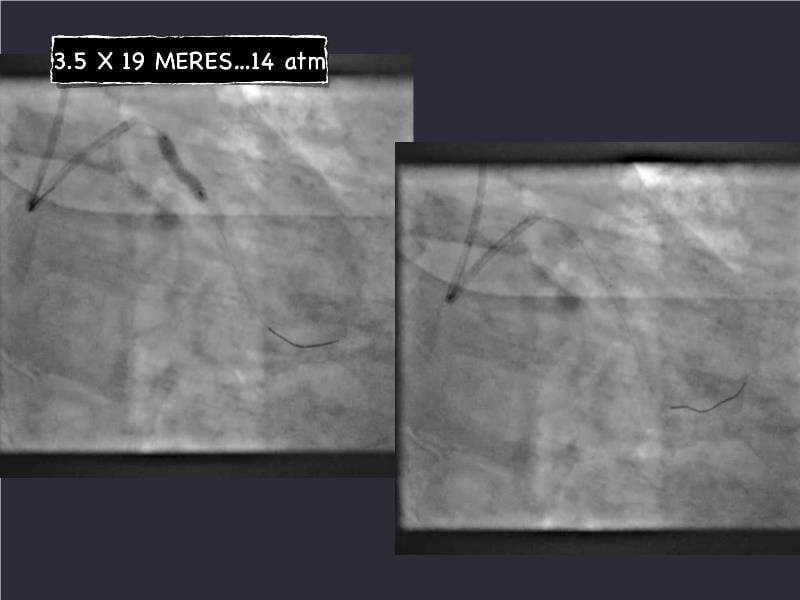

This session is a valuable resource for grasping innovative strategies in handling bifurcation and extended diffuse lesions through dedicated stenting solutions. Explore insights into the advanced Myval next-generation THV technology, unveiling its distinctive features, procedural advantages, and clinical outcomes across a diverse patient pool. Gain understanding into the CorAlign technique, ensuring accurate commissural and coronary alignment while maintaining coronary access. Additionally, delve into the techniques for precise sizing, positioning, and deploying of Myval THV.

- To understand novel tools and techniques for effective management of bifurcation lesions and long diffused lesions using dedicated stenting solutions